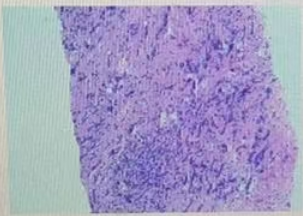

·乳腺彩超

1、右乳9点见一个低回声区,大小约0.53*0.63cm,呈直立生长,边缘成角、毛刺,内部回声不均匀,肿块内未见强回声,BIRADS 5类;

2、右乳10点见一个低回声区,大小约1.4*0.9cm,边缘成角、毛刺,内部回声不均匀,肿块内未见强回声,BIRADS 5类。

图1乳腺彩超结果